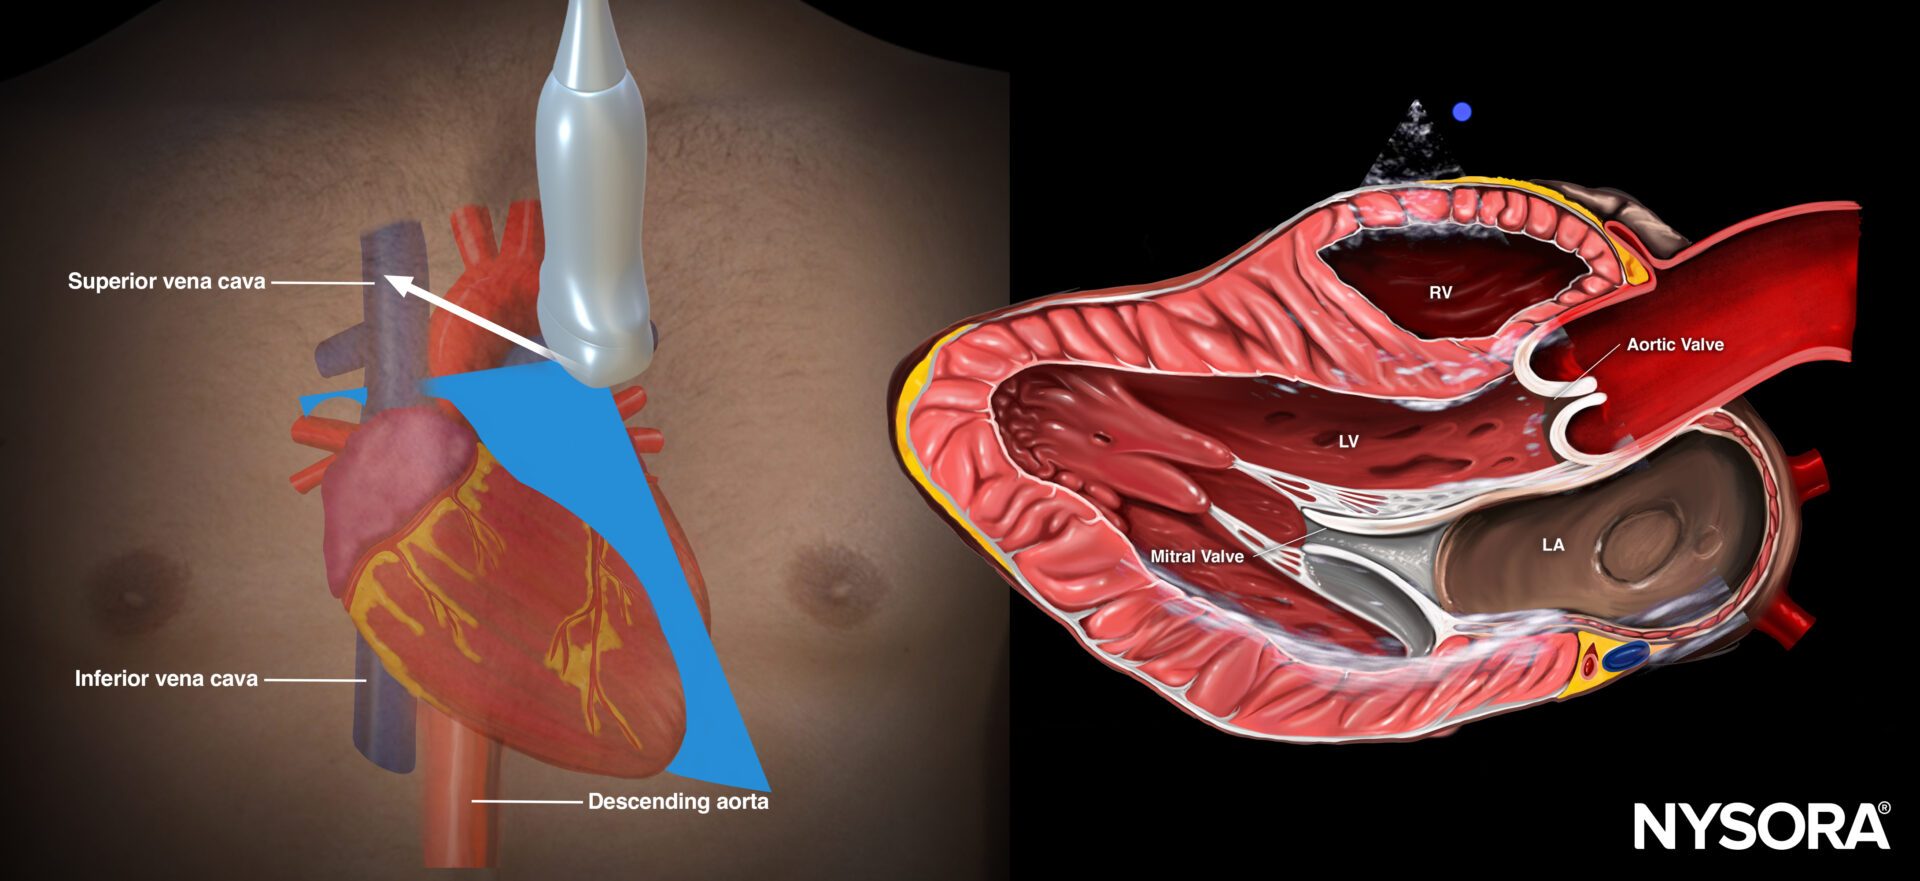

- When it is difficult to differentiate pleural from pericardial effusion, use the parasternal long-axis view to locate the fluid in relation to the descending thoracic aorta and the pericardium.

- Anterior/superficial to the descending aorta and the pericardium: Pericardial effusion (rat tail sign).

Posterior/deep to the descending aorta and the pericardium: Pleural effusion.

Sonoanatomy of the heart in the parasternal long-axis view. Left ventricle (LV), left atrium (LA), mitral valve, aortic valve, right ventricle (RV).

Reverse Ultrasound Anatomy of the heart in the parasternal short-axis view. Left ventricle (LV), left atrium (LA), mitral valve, aortic valve, right ventricle (RV).